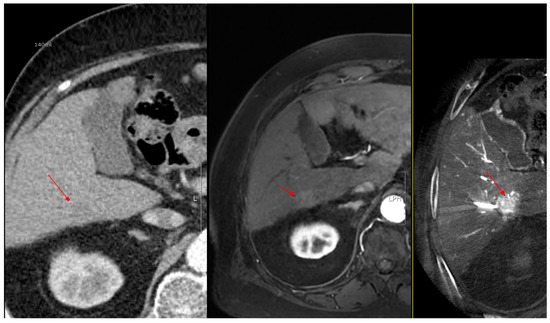

Figure 2. CT images from a patient with hepatocellular carcinoma undergoing angio CBCT-guided RFA. (Top): pre-procedural CT (portal venous phase; lesion 128.7 HU, red arrow = HCC mass). (Bottom): intraprocedural angio CBCT (lesion 1499.7 HU, red arrow with star = HCC mass). ΔHU = 1298.0 HU. (intra lesion − intra background) − (pre lesion − pre background).

As shown in Figure 1, angio-CBCT allows for higher visibility of the target mass, as reflected in the ΔHU values. This can be visually confirmed in several cases. Representative cases in Figure 2 and Figure 3 demonstrate how the target mass is much more conspicuous to the operator on angio-CBCT compared to pre-procedural CT. In Figure 4, a mass, which was nearly invisible on pre-procedural CT, was identified through angio-CBCT, aiding the targeting process. Figure 5 shows a case where a mass with discordance between USG and CEUS was confirmed using angio-CBCT, leading to needle repositioning and achieving complete ablation. Finally, Figure 6 illustrates a case where a residual tumor was identified on angio-CBCT and re-ablation resulted in complete ablation.

Moreover, a key observation in our study is that intraprocedural lesion conspicuity increased markedly despite a lower contrast load. This was quantified as the ΔHU change between preprocedural imaging and intraprocedural acquisitions (CBCT group: median 290.1 HU [IQR, 197.5–414.1] vs. conventional group: −10.5 HU [IQR, −17.9–16.5]). (Figure 1) This increase in conspicuity translated into actionable, on-table decisions: electrode repositioning in 14.3% of cases and planned re-ablation in 21.4% (Table 2). Practically, the ability to “see better” at critical moments appears to tighten the imaging–therapy feedback loop, increasing the likelihood of achieving complete ablation within a single session and potentially reducing early local failure.